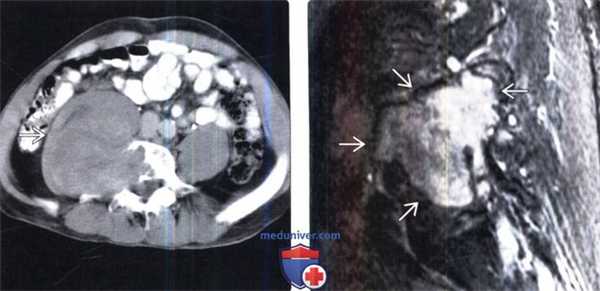

(Слева) Аксиальный срез, Т1-ВИ с КУ: крупная неравномерно-дольчатая ЗООПН забрюшииного пространства, характеризующаяся неоднородным контрастным усилением сигнала.

(Справа) Аксиальный срез, Т1-ВИ с КУ нижнегрудного отдела позвоночника: накапливающее контраст объемное образование в просвете левого неврального отверстия, деформирующее тело и задние элементы позвонка. Позади ножки диафрагмы слева также видна накапливающая контраст нейрофиброма.